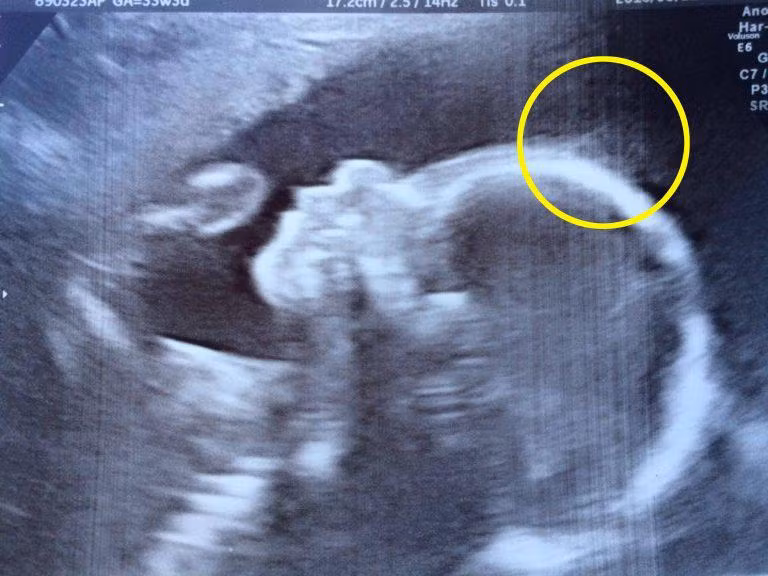

Trước khi Holly Gent chào đời, vào tuần thứ 20, bố mẹ em được thông báo con gái sẽ có “Một chút tóc” và trong suốt thời gian siêu âm, những lọn tóc đó hiển thị trên hình ảnh 3D và 2D vô cùng rõ nét. Bố mẹ cô bé coi đây là chuyện bình thường.

Hình ảnh tóc của cô bé Holly có thể được nhìn rõ từng sợi từ khi mới chỉ siêu âm tuần 20.